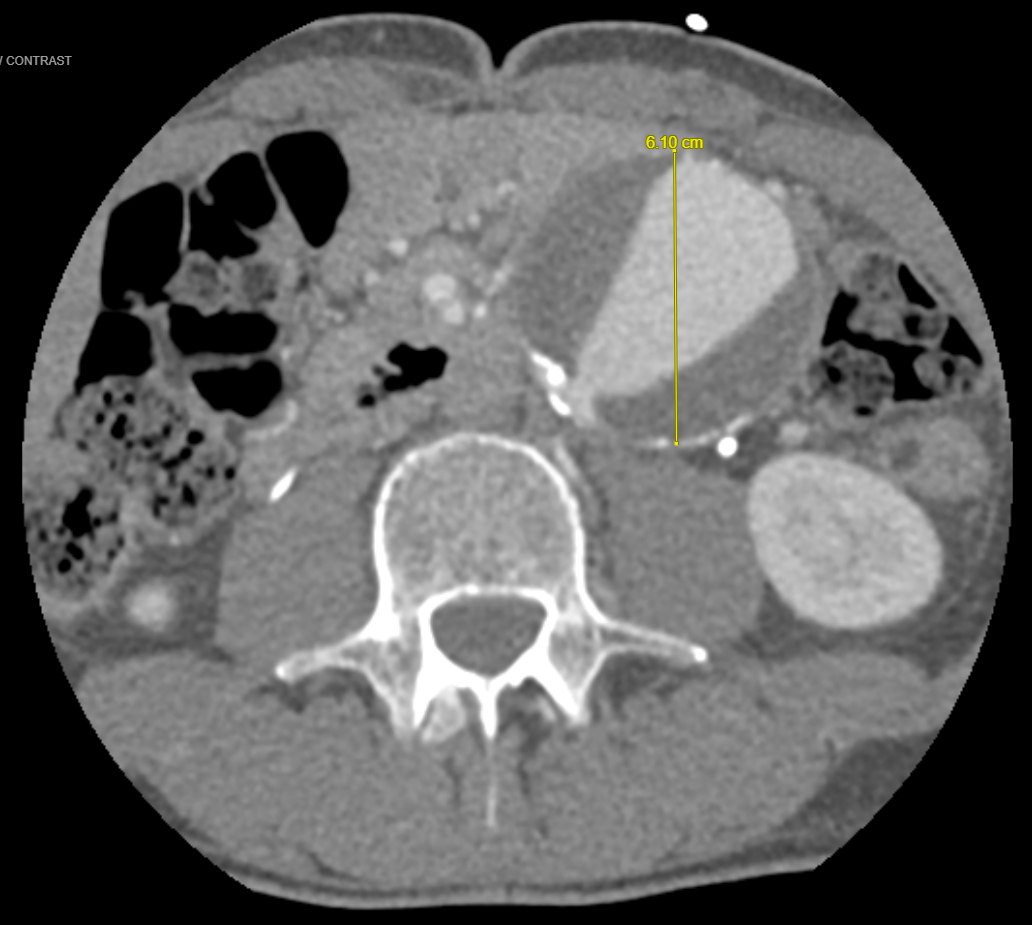

Case Presentation: A 42-year-old male with a history of hypertension and chronic Stanford type A/DeBakey I AD post aortic arch and valve repair (11 years prior), with thoracoabdominal dissection and aneurysmal changes, presented with difficulty in speech and unsteady gait. Blood pressure (BP) was 183/102 mmHg. ECG showed normal sinus rhythm. The last well-known was 45 minutes before the presentation; the National Institutes of Health stroke scale (NIHSS) was 6. The non-contrast CT head was unremarkable; CT angio showed left M2 MCA occlusion in the Sylvian fissure, Stanford type A AD with flaps crossing the origins of the brachiocephalic, left common carotid, and left subclavian. CT head perfusion revealed 65 cc of ischemic penumbra in the left MCA territory and a core infarct of 7 cc. MRI of the brain revealed an acute infarct in the left frontal and parietal lobes; CT chest/abdomen/pelvis showed an aneurysmal thoracoabdominal aorta (descending: 6x5.9 cm; suprarenal: 4.1x4 cm; infrarenal: 5.4x6.1 cm) with mural thrombus in the false lumen. On day 0, his mental status declined, NIHSS increased to 16 and he required intubation. He was taken for emergent percutaneous intracranial mechanical thrombectomy (MT) through left carotid artery access by vascular surgery, followed by interventional neurology rescue and achieved thrombolysis in cerebral ischemia score (TICI) 2C. He was extubated on day 1, and NIHSS improved to 3 over the next 3 days.